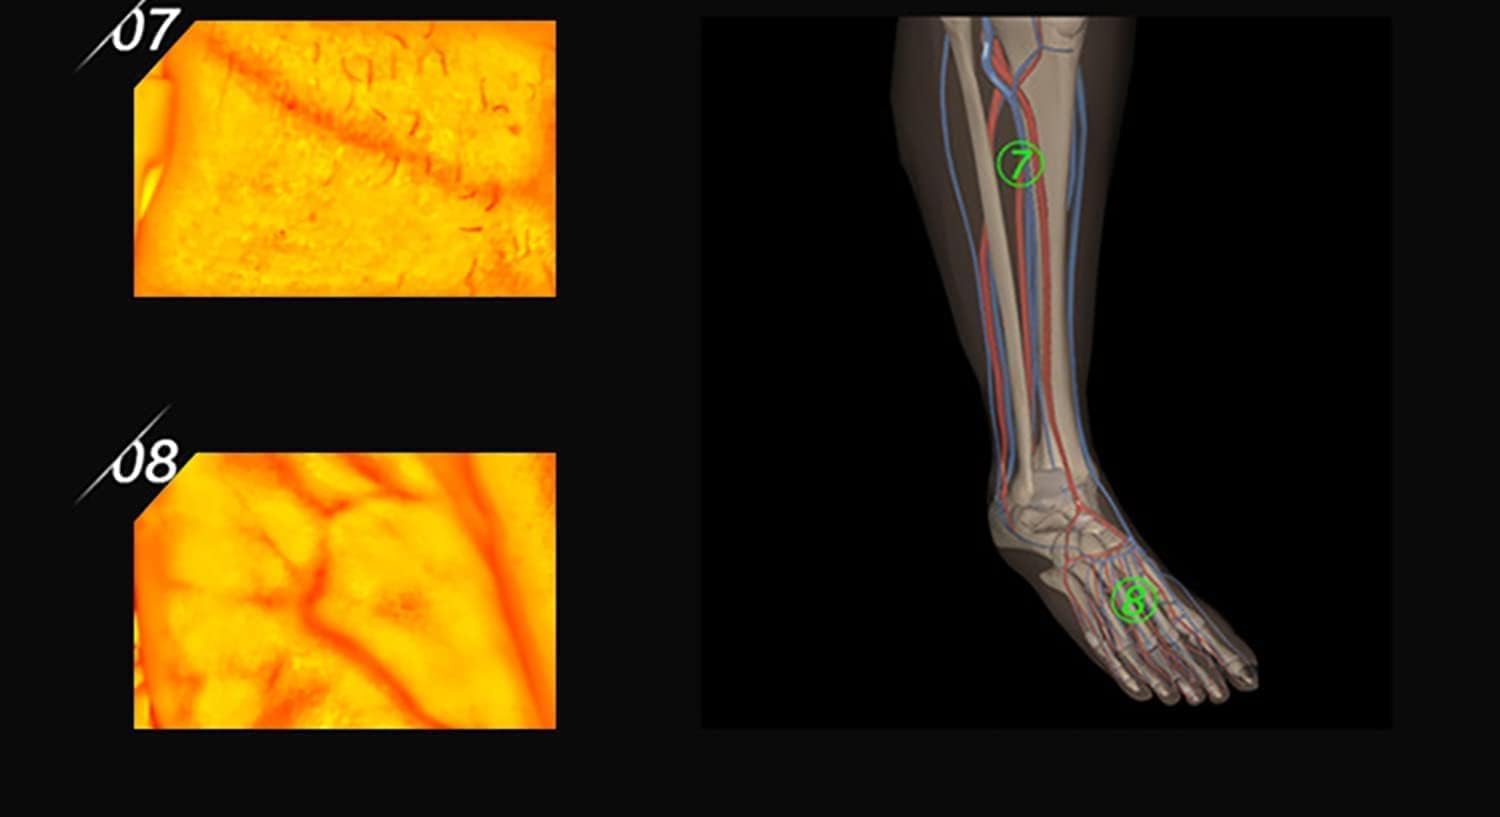

Adults Children Suitable Vein Viewer Display Lights Imaging Find Vein Medical Vein Finder Vein Viewer, for Hospitals

Adults Children Suitable Vein Viewer Display Lights Imaging Find Vein Medical Vein Finder Vein Viewer, for Hospitals

Our medical vein finder device adopts the principles of hemoglobin strong absorption of infrared light,

designed the helpful vein finder device, which consists of infrared vein collector & vein recognition system